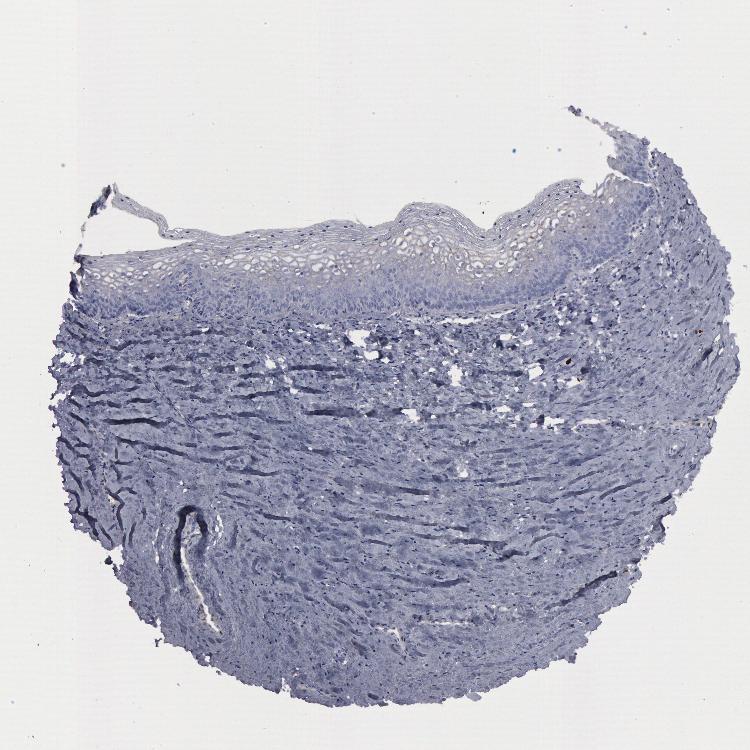

VAGINA - Antibody stainingi

Antibody staining in the annotated cell types in the current human tissue is reported as not detected, low, medium, or high, based on conventional immunohistochemistry profiling in selected tissues. This score is based on the combination of the staining intensity and fraction of stained cells.

Each image is clickable and will lead to virtual microscopy that enables deeper exploration of all samples and also displays staining intensity scores, fraction scores and subcellular localization as well as patient and tissue information for each sample.

Antibody HPA001040Antibody HPA001391Antibody CAB020817

Squamous epithelial cells Not detectedNot detectedNot detected